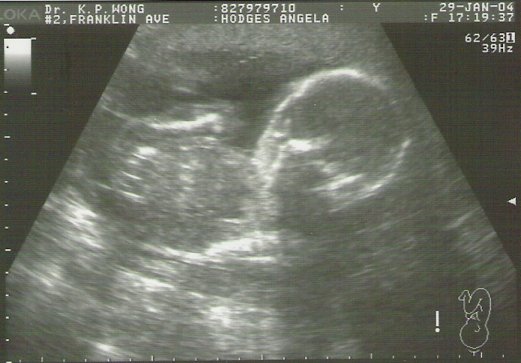

First Ultrasound

Here's the very first baby picture. Not quite ready to star in the credits of the Drew Carey show but getting there all the same. The doctor did several measurements on screen and everything is the right size and shape for about 12 weeks of growing. Fingers crossed everything will go smoothly from here.

I'm not too sure but I think it is a shot of the baby's right hand side with their arm up. We also have a video coming where you can see the baby moving their arms around too which I'll convert and post as soom as we get it back.